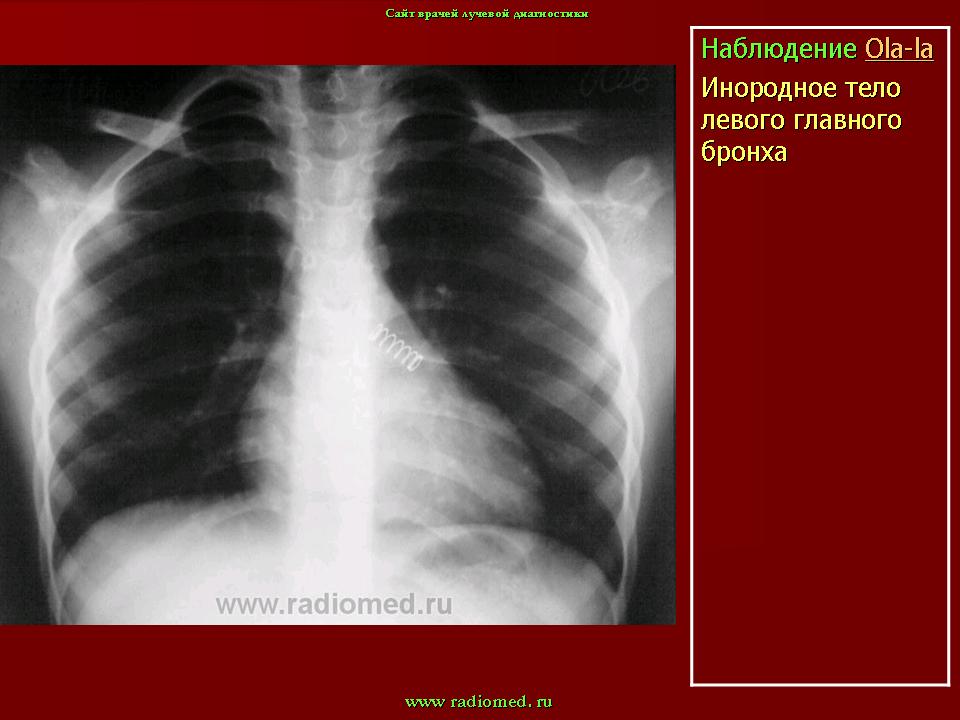

Инородные тела.

Приложения:

1.in_.slayd1_.jpg2.in_.slayd2_.jpg